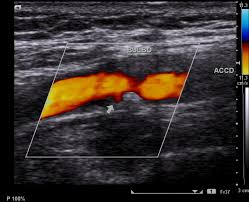

- 젤을 바른 후 초음파 탐촉자를 경동맥 위에 대고 영상 관찰

- 혈류 속도 측정과 플라크 유무 확인

- 혈류 속도 증가 여부